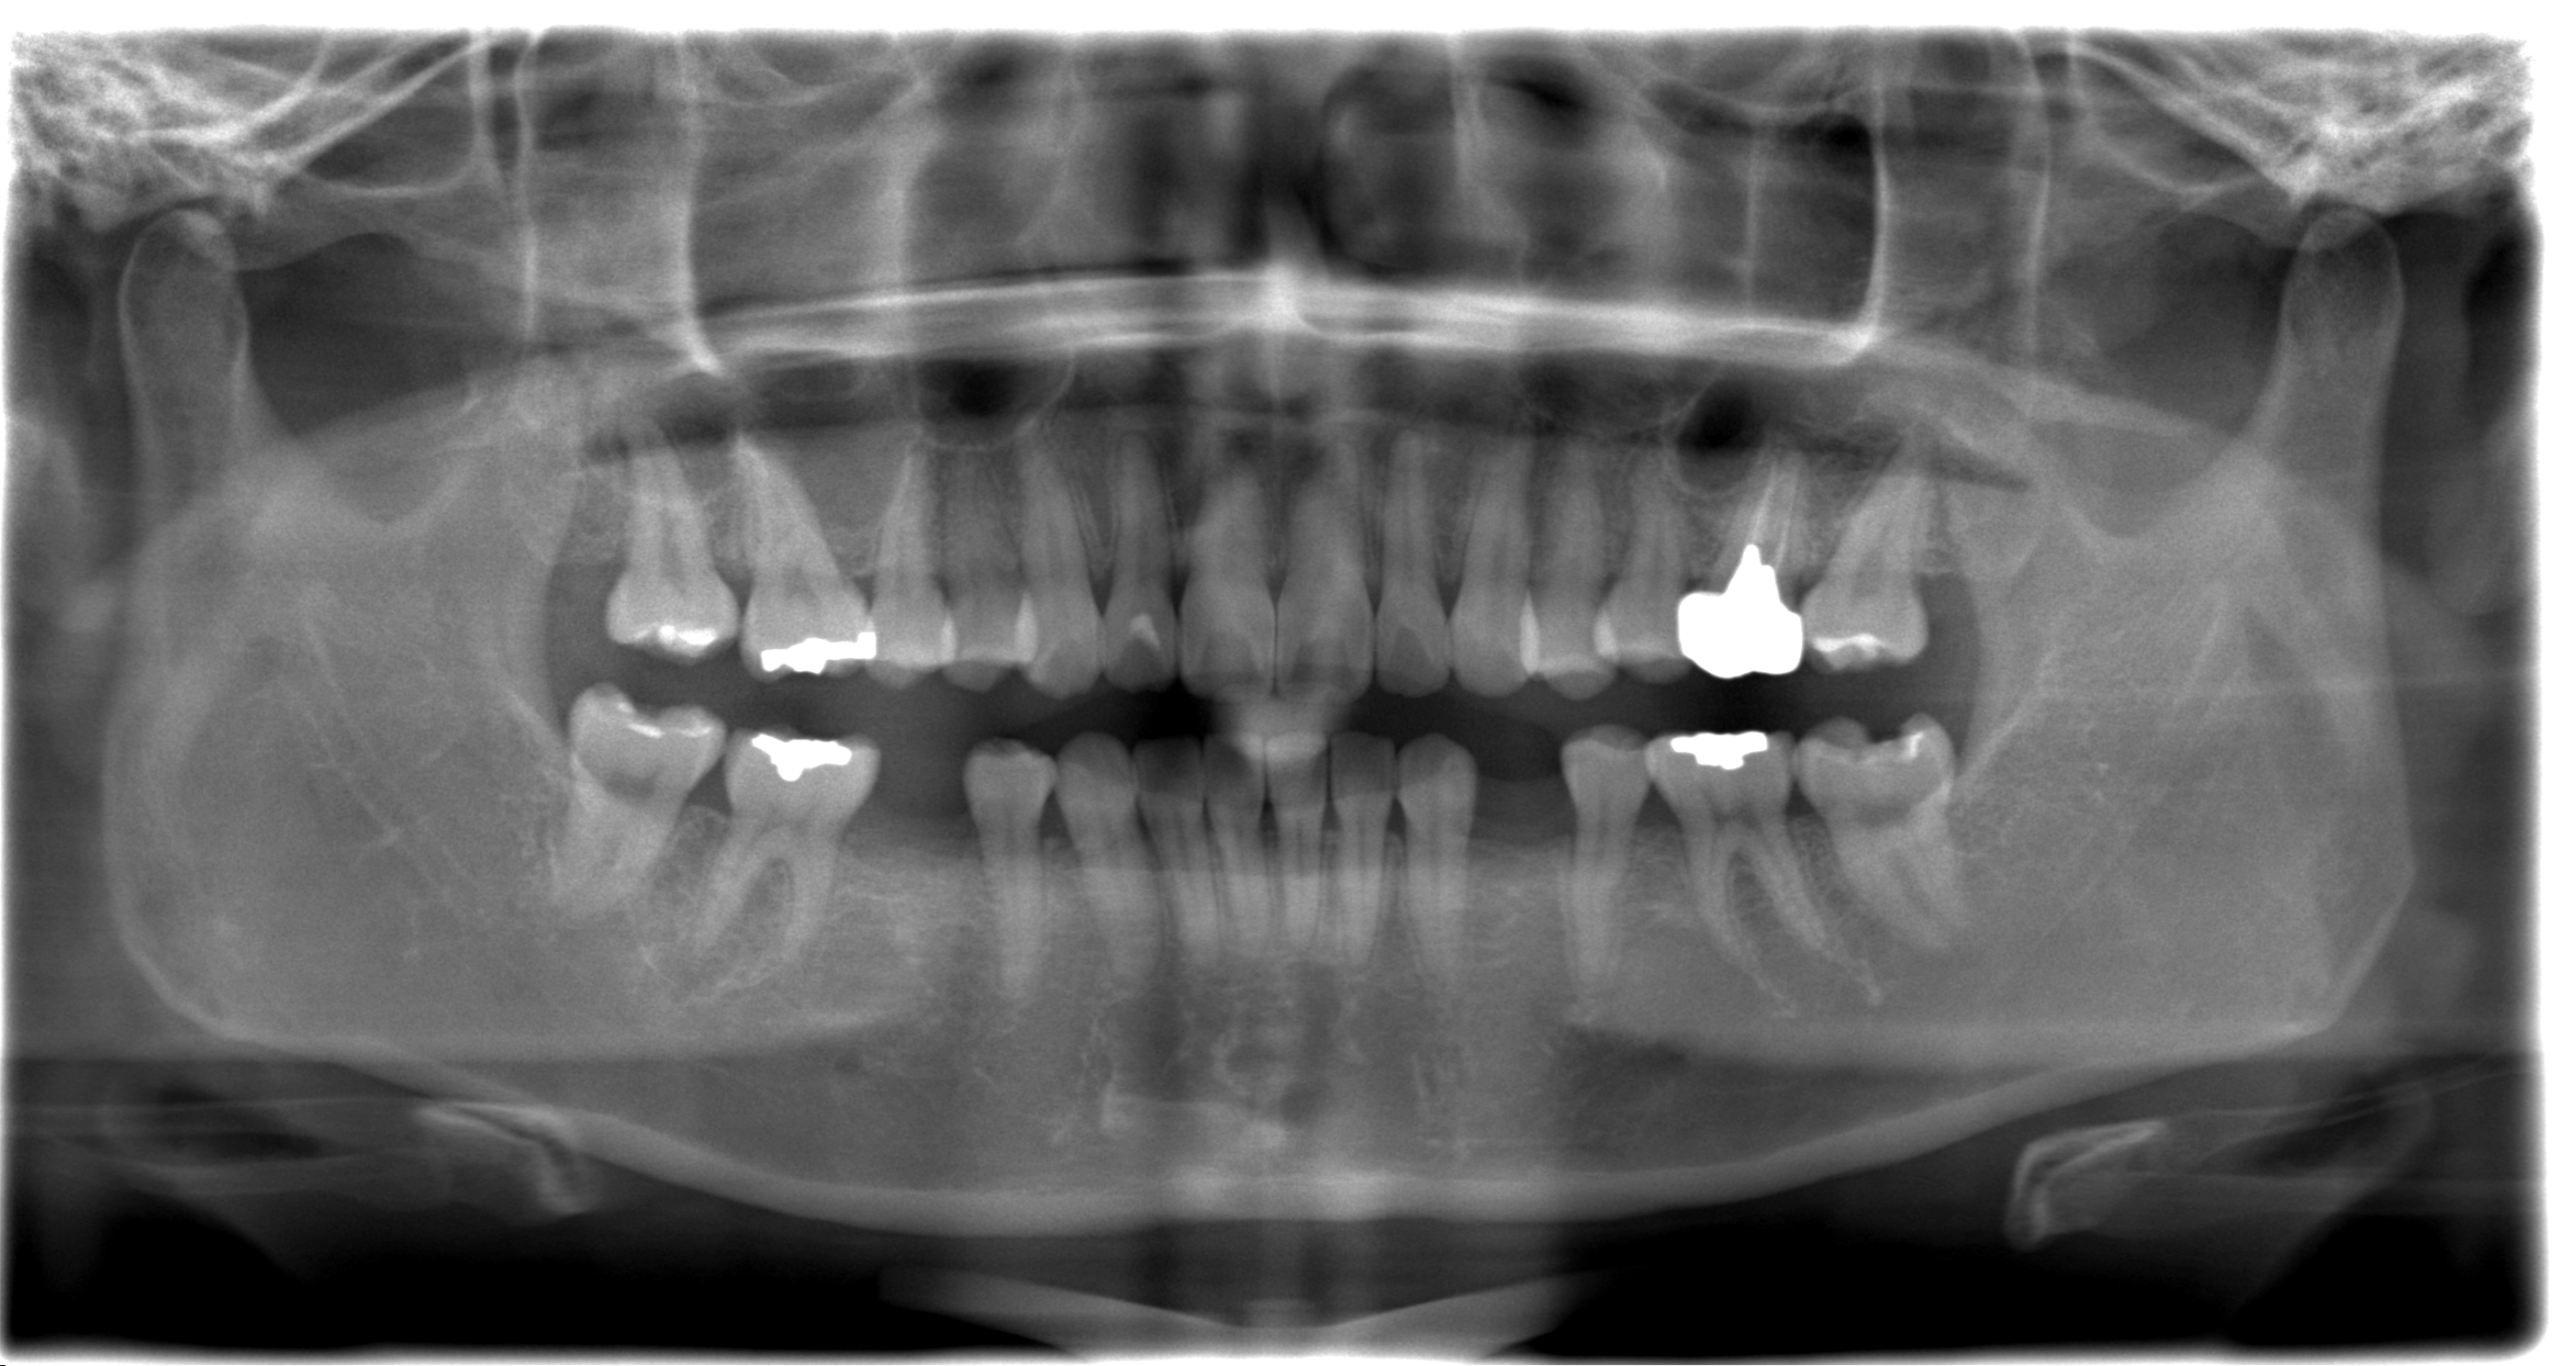

before

after

部分的な治療ではなく、咬合から全体的な調和を図ることで長持ちするインプラント治療が実現出来ます。

結果的に長期的なお口の中の安定と安心してなんでも噛める環境が実現できたと思います。